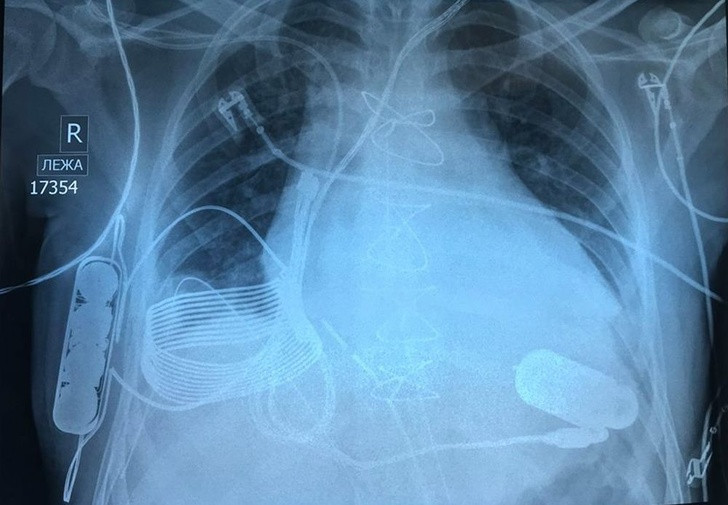

7. Một bức hình chụp X-quang ngực ghi lại một trái tim sinh học với sạc không dây.